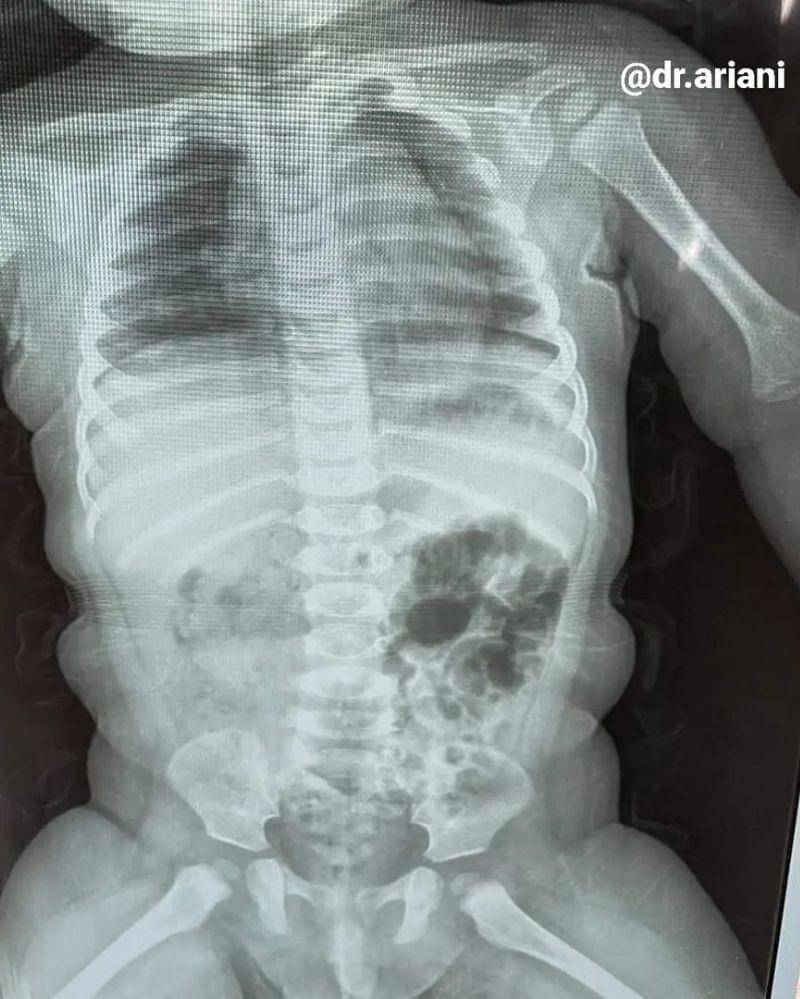

Mama Selny dan suami pun langsung membawa putranya ke rumah sakit untuk selanjutnya melakukan pemeriksaan melalui X-Ray. Hasilnya, pecahan kotak termometer yang berhasil tertelan oleh Gema ternyata tersangkut di saluran cerna, tepatnya di usus besarnya.

Setelah melakukan pemeriksaan X-Ray, dokter menganjurkan melakukan observasi selama 2 x 24 jam untuk melihat keluhan yang ditimbulkan akibat pecahan benda tajam yang masuk ke dalam tubuh Gema.